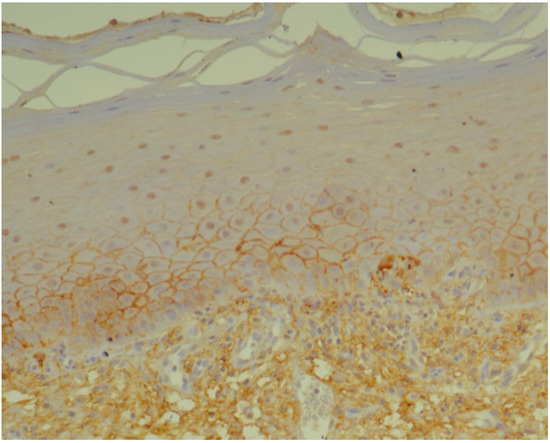

2.2. Histopathology and Immunohistochemistry

3.1. Histopathology and Immunohistochemistry